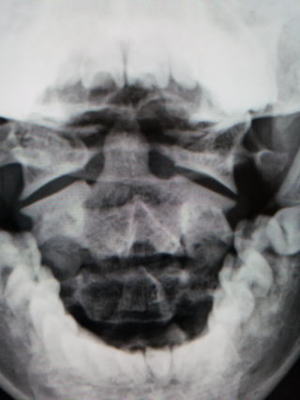

子供が朝起きたら首が痛くなって、痛む方と反対側に顔をひねるようにして訴える病気です。はっきりした誘因が無い場合もありますがマット運動などでの外傷が契機となることもあります。ほとんどが子供に起こりますが、まれに大人にも発症することがあります。今回、格闘技で頸椎を捻られてから首に引っかかり感があるとのことで来院されたまれな成人例をご紹介します。(本人の許諾を得ています)

環軸関節は、第1頚椎であるリング状の環椎と第2頚椎である歯突起という突起を持った軸椎で形成されます。主に首を左右に向く動作を担っています。この環軸関節がずれてしまい、痛みで首が動かせなくなる状態を環軸関節回旋位固定と言います。

初診時(受傷後一ヶ月)

左:レントゲン開口位正面像

歯突起が右にずれています。また下顎が左に向いています。

右:MRI 横断像 歯突起が右方向にずれています。歯突起を止めている環椎横靱帯の左側が高信号(T2強調像)

ソフトカラーを装着して安静をはかりながら、京大病院を受診して頂きました。

*成人例は極めてまれで、論文もわずかしか無い状況でした。一般的に改善しない場合は手術が必要なこともあり、念のため京大病院整形外科脊柱外来にコンサルトしています。

一ヶ月後

頸椎のソフトカラーを装着し、痛みは改善しました。画像上も歯突起はほぼ中央に収まっています。可動域も良好で引っかかり感は消失しています。

MRIでは、初診時に腫れていた環椎横靱帯の左側は縮小しています。

|

今回、MRI像の経時的変化をみると、当初、外傷性に環椎横靱帯の片側性損傷が起こり、これにより同靭帯の腫れ(浮腫)が一側に生じた結果、歯突起が中央より偏位したのではないかと思われます。その後、局所安静により腫れが引いて歯突起が中央に戻り、病状が改善することが示唆されます。